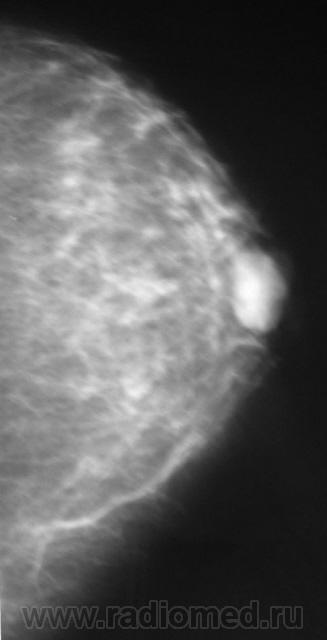

Ещё одна интересная маммография

Жалоб пациентка не предъявляет, просто иногда ощущает дискомфорт в мол.железах.

Кистозный ФАМ с одной стороны просто ФАМ с другой (где право-лево не указано на снимках)

Где прямые, где косые? Вероятно кисты, но могут быть и фиброаденомы, надо УЗИ и при кистах - пункционное удаление содержимого, при фиброаденомах - секторальная резекция.

А, мне, что-то больше симпатично, как "фиброаденомы".

Гадать кисты это или фиброаденомы без УЗИ - дело не благодарное, почему кисты ставлю на первое место потому, что чаще кисты бывают множественными.